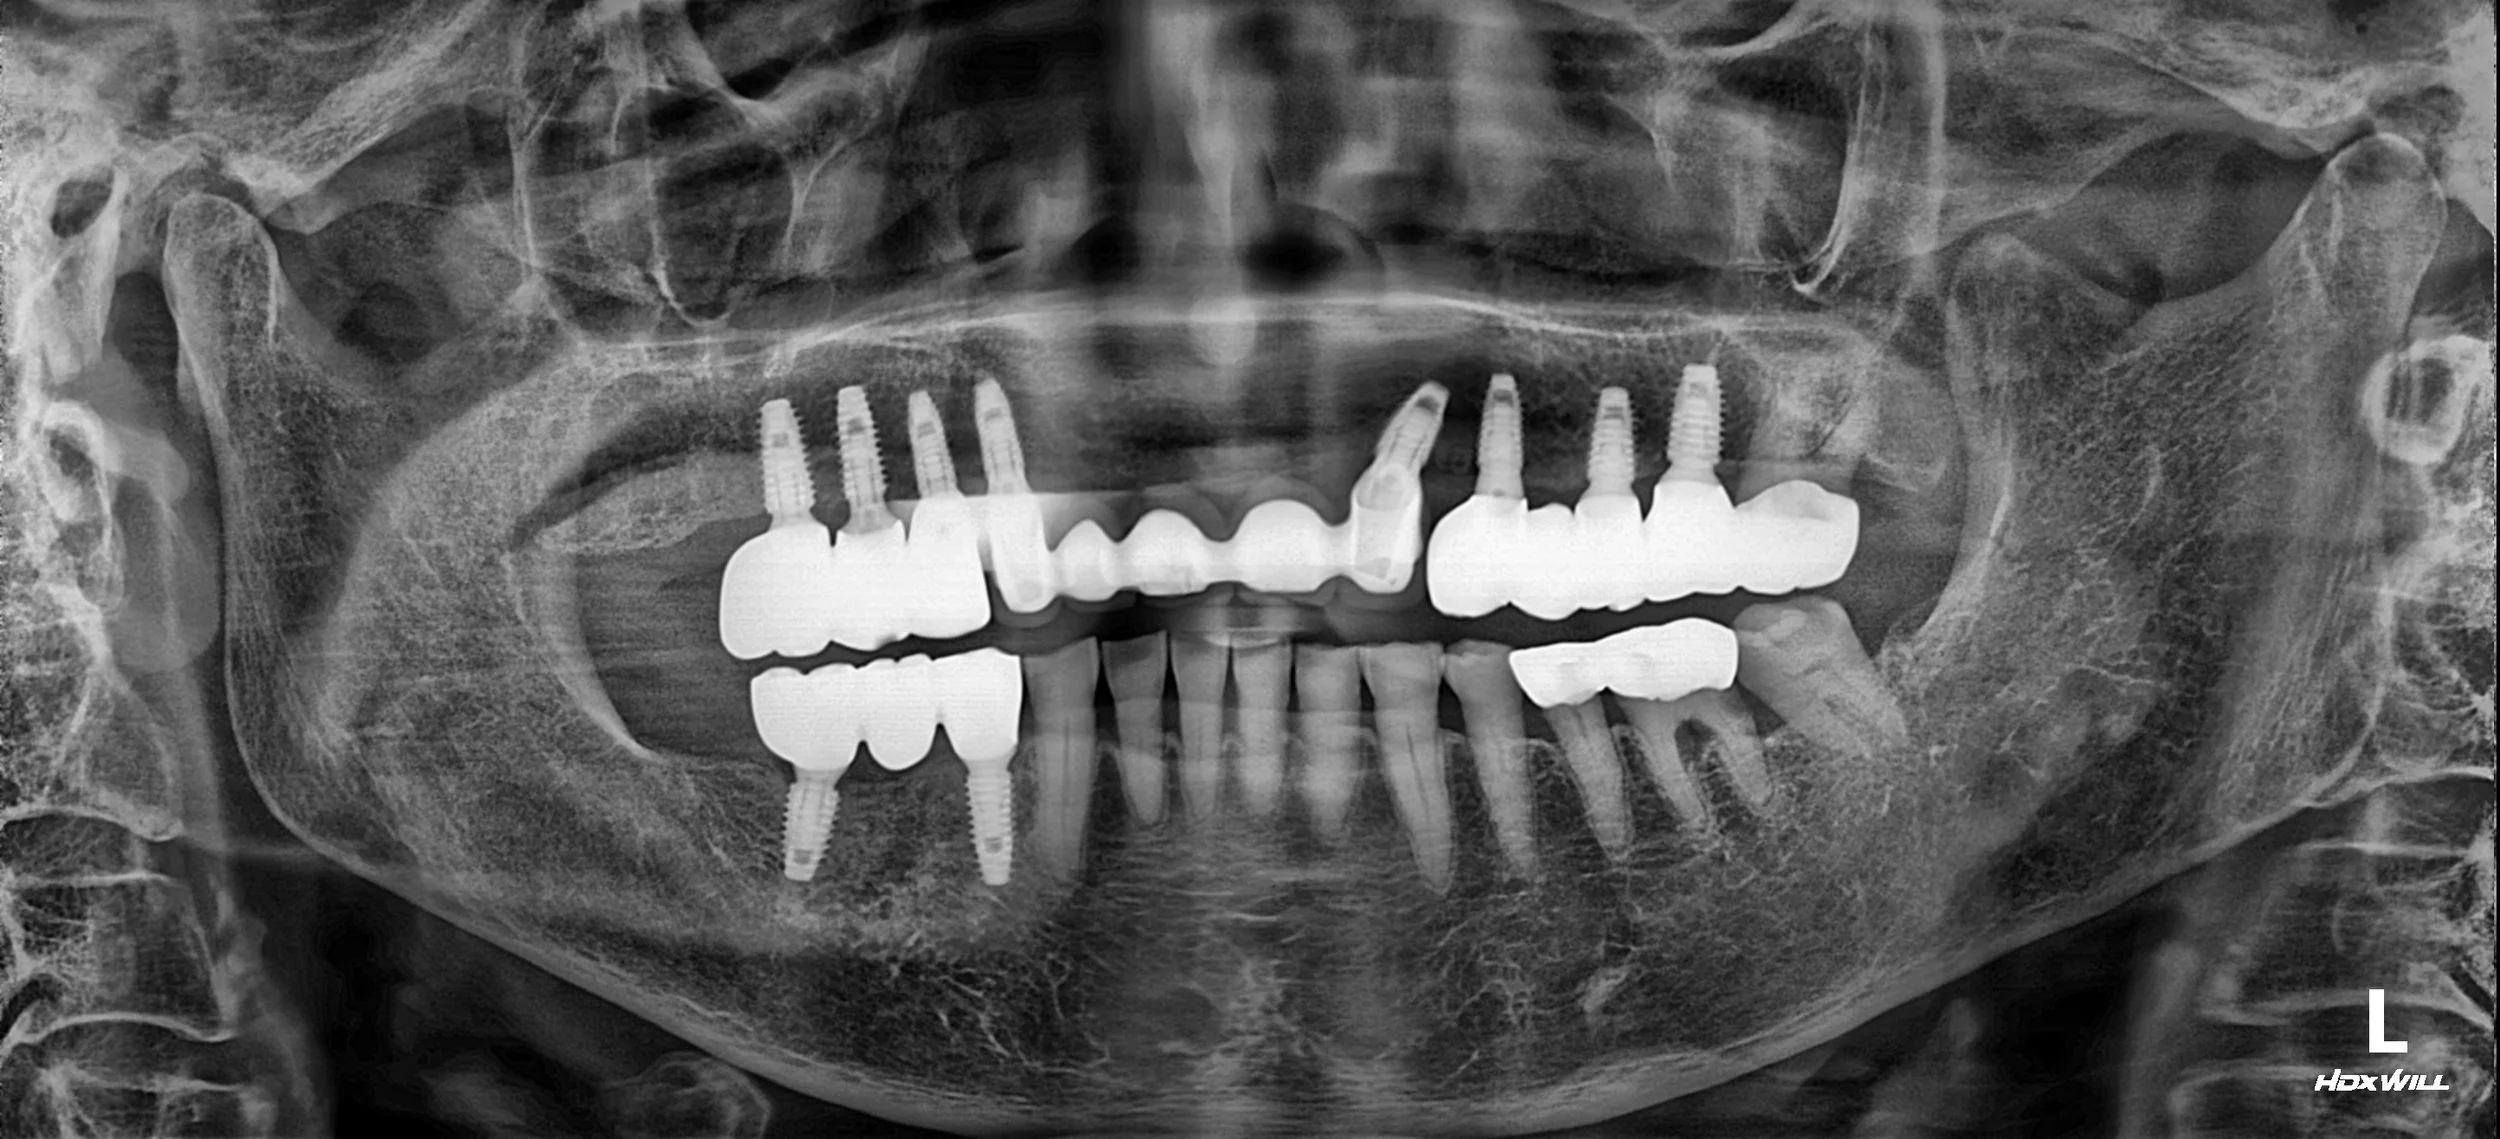

OPG - BEFORE